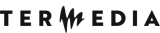

Flexion MRI:

Inter-segmental angles of flexion were recorded at C5-6 and C6-7 on T2W sagittal images by drawing a line along the middle borders of the vertebrae in the flexion position according to the method given by Schroder [17] (Figure 4).

LOA of posterior dura with anterior displacement was seen in all the patients (100%) on flexion MRI (Figure 7). LOA involved the whole of the posterior dura (bilateral) in 13 patients (76.4%) and only one side in 4 patients (23.5%). Maximum LOA was seen at the C6 level in 10 patients (58.8%), followed by C5-6 intervertebral disc level in 5 patients (29.4%), and C5 and C6-7 level in one patient each (5.8%). This LOA of the posterior dura was seen in 11 patients (64.7%) on neutral position MRI, as well (Figures 8 and 9). On evaluating axial T2W and T2 FFE images for LOA of posterior dura, mutual consensus was reached by 2 radiologists that it was better visualised on T2 FFE images (Figure 9). The mean thickness of this LOA on flexion was 3.7 ± 0.66 mm (mean ± 2SD).

Figure 7

Sagittal T2W image in the flexion position in a patient showing anterior displacement of the posterior dura (white arrows). The flow voids are also seen in the posterior epidural space

Posterior epidural flow voids were seen in 13 patients on T2W images on flexion MRI (76.4%) (Figure 7). Almost all the patients (16 out of 17) showed thick crescentic-shaped homogenous intense enhancement in the posterior epidural space in the flexion position (Figure 10). The imaging findings are summarized in Table 2.

Figure 10

Sagittal and axial T1W post-contrast image of the cervical spine in flexion position showing intense enhancement in the posterior epidural space (black arrow) extending from the C3 level to the T2 level (white arrows) and involving the bilateral sides (100% of the posterior dura is displaced forward)

The mean inter-segmental angle of flexion at C5 and C6 was 9.2°, and at C6 and C7 it was 6°.

Flexion MRI shows the LOA, cord atrophy, and posterior epidural enhancement very well. On flexion MRI, all our patients showed forward displacement of the posterior dura, which is considered a hallmark of HD. This LOA of the posterior dura has been reported in various previous studies [5,18,21-24]. A study by Lehman et al. reported 100% specificity for the same, but with a lower sensitivity and false negative rates of LOA in a few patients [18]. These patients had a higher mean age (37.8 years), and it is believed that the findings of HD decrease with advancing age [1,15,18]. This forward displacement in the patients, measured as laminodural space (LDS) distance as stated by Boruah et al., can range from 3 to 9.8 mm, with a mean distance of approximately 5.99 mm [22]. However, our study showed this distance to be approx. 3.7 ± 0.66 mm (mean ± 2SD). This is lower than the distance measured in the study done by Boruah et al., which could be due to the larger number of patients included in their study. The most common site for maximum forward displacement of the dura in our study was at C6, seen in 58.8% of patients. The centre of displacement was also reported to be the C6 vertebra in the studies done by Hirayama et al. and Yin et al. [1,25]. On reviewing the axial sections for dural detachment from the adjacent lamina on flexion MRI in our patients, it was found to be bilateral in 13 patients (76.4%) and unilateral in 4 patients (23.5%). On searching the literature, we could not find any study on the evaluation of this imaging attribute in HD.

In another study done on HD, it was seen that the displacement of the posterior dura was also present in 46% of the normal population (controls); however, the extent of forward displacement was significantly less in them (0.99 ± 0.97 mm) compared to patients with HD (6.7 ± 0.78 mm). This forward displacement in controls was probably compensated by a corresponding increase in spinal canal volume, thus sparing the cord from compression [26]. However, the forward displacement in controls has not been reported by other studies [1,18,25]. Further research is required to study this imaging parameter in healthy subjects.

Crescentic homogenous enhancement was seen in the posterior epidural space on post-contrast flexion T1W images in almost all (93.7%) of the patients, which is in accordance with various studies [5,18,23]. Only one patient did not show enhancement: a follow-up case of HD aged 46 years. This can be explained by the fact that the findings of HD decrease with chronicity of the disease [1]. The enhancement has been attributed to the congestion of the posterior internal vertebral venous plexus [3]. There are 3 theories explaining the engorgement of venous plexus: 1) an anterior shift of the dura results in negative pressure in the posterior spinal canal, with resultant increased flow to the posterior internal vertebral venous plexus [6]; 2) the anterior internal vertebral venous plexus is compressed due to an anterior shift of the dura with resultant dilatation of the posterior internal vertebral venous plexus [5]; and 3) the venous drainage of the jugular veins is reduced in neck flexion, which compresses the venous return of the internal venous plexus [6]. Flow voids were seen in 76.4% of patients in the posterior epidural space on T2W images, which is in concordance with previous studies [10,11,13,22]. The aforementioned findings of forward displacement of the posterior dura, crescentic homogenous enhancement, and flow voids in the epidural space on flexion MRI are diagnostic of HD.

We also measured the inter-segmental angles of flexion on sagittal MRI at the C5-C6 and C6-C7 levels to see if the angle and ROM were greater in the lower cervical region in HD, because the surgical intervention is dependent on these findings. Maximum flexion was observed at the C5-C6 level followed by C6-C7 with a mean of 9.2° and 6o, respectively. As per Xu et al. also, the maximum flexion was seen at the C5-C6 level followed by the C6-C7 level, where the angles of flexion were 11.9° and 10.8°, respectively, whereas similar angles in controls were 5.4° and 5.6°, respectively [8]; our observations were similar except for the fact that we did not study angles of flexion in normal subjects. This shows that there is increased ROM in patients with HD, which could be an important factor related to the severity of the disease. Furthermore, because this increased ROM is amenable to surgical correction, which in turn can halt the progression of disease, mentioning the angle in the report becomes very important.

MRI in the flexion position is the gold standard for HD, which shows the hallmark findings of loss of posterior dural attachment, enhancement of posterior epidural venous plexus, presence of flow voids, and increased inter-segmental angle of flexion. Increased range of flexed motion in patients with HD must be reported because surgical intervention is dependent on it. Careful evaluation of neutral-position MRI for the loss of dural attachment (which can be a subtle finding), asymmetric lower cord atrophy, T2 hyperintensity, and abnormal cervical curvature is of utmost importance because it prompts the radiologist to include a flexion sequence in the MR examination to confirm the findings of HD. Thus, familiarization of imaging findings of HD on neutral and flexion MRI and adopting a standardized MR imaging protocol can help in prompt diagnosis and early rehabilitation of the patient.